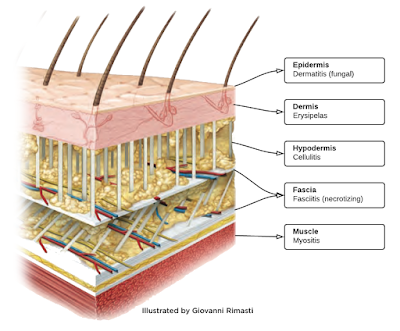

The code selection will be determined upon the following: Check the pathology reports, if any, to confirm Morphology (whether the neoplasm is benign, in-situ, malignant, or uncertain) Technique Topography (anatomic location) The size Tissue Level Type of closure required Layers. You will find using coupon code very simple with isCoupon. There are several considerations to be aware of before assigning a code for lesions and soft tissue excisions. You just need to select an appropriate discount code or deal, copy and paste in the discount code box at the checkout step. All discount programs are thoroughly tested before being public, therefore, you can rest assured that all code works. You can get all the amazing discounts from many stores around the world. IsCoupon is a free site to help you find many coupon codes.